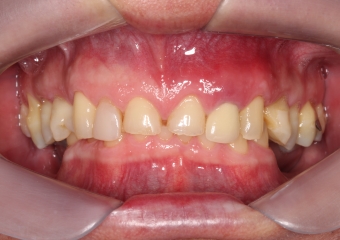

Imagem inicial em 2014

Sorriso inicial, em 2014